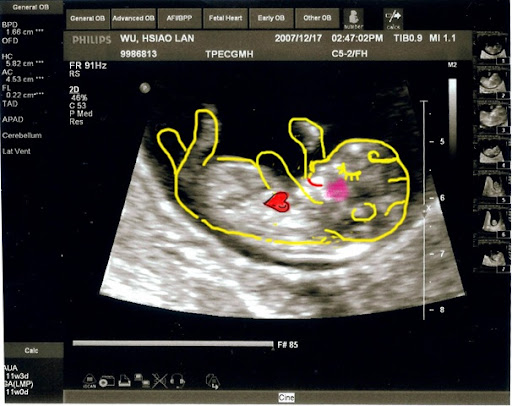

這次的超音波就不用畫圖說故事了吧 !!

再看不懂就只能說.. 你是火星來的嗎

醫生也細心地講解各部位的發育

小baby還一邊揮舞著小手 看起來也像是在吸手指..